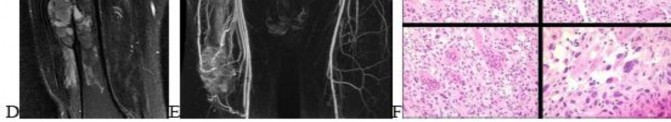

A 15-year-old male presents with deep knee pain awakening him at night. Radiographs show a permeative destructive lesion in the distal femoral metaphysis with a 'sunburst' periosteal reaction and Codman's triangle.

Biopsy confirms high-grade conventional osteosarcoma. What is the most critical prognostic factor for long-term overall survival in this patient?

Explanation

For localized high-grade osteosarcoma, the most important prognostic indicator is the histologic response to neoadjuvant chemotherapy. This is evaluated during the definitive resection. A 'good response' is typically defined as greater than 90% or 99% tumor necrosis. Patients who achieve this level of necrosis have a significantly improved disease-free and overall survival rate compared to 'poor responders' who have extensive viable tumor cells remaining.